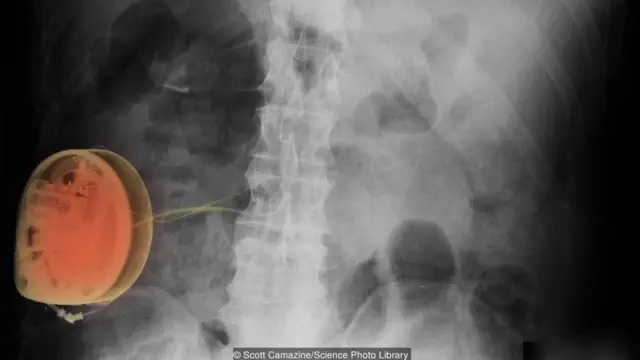

इमेज स्रोत, Spl